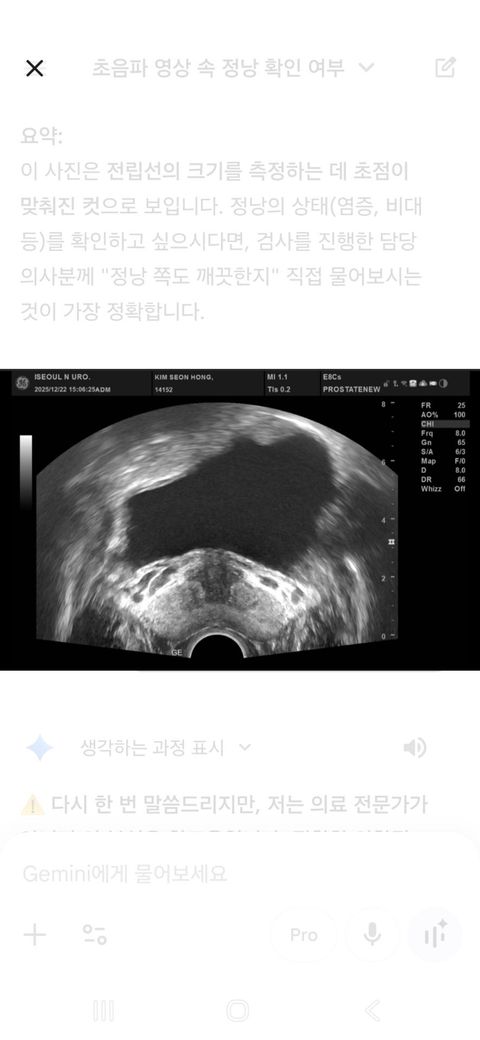

• 2번 째 사진

초음파를 통해 전립선염을 진단하는 것은 아닙니다. 전립선염이 의심될 때 전립선 초음파를 시행하는 것은 전립선염에 의한 합병증으로 농양 등의 발생을 확인하는 것이며 전립선 폐색을 유발할 수 있는 구조적인 문제가 있는지 확인하는 것에 주목적이 있습니다. 전립선염은 초음파만으로 진단하는 것이 아니며 혈액검사나 정액검사 임상 증상을 종합하여 판단하게 됩니다. 올려주신 사진만으로 전립선염 여부를 알기는 어려우며 농양이나 구조적인 이상은 없는 것으로 판단할 수 있습니다.